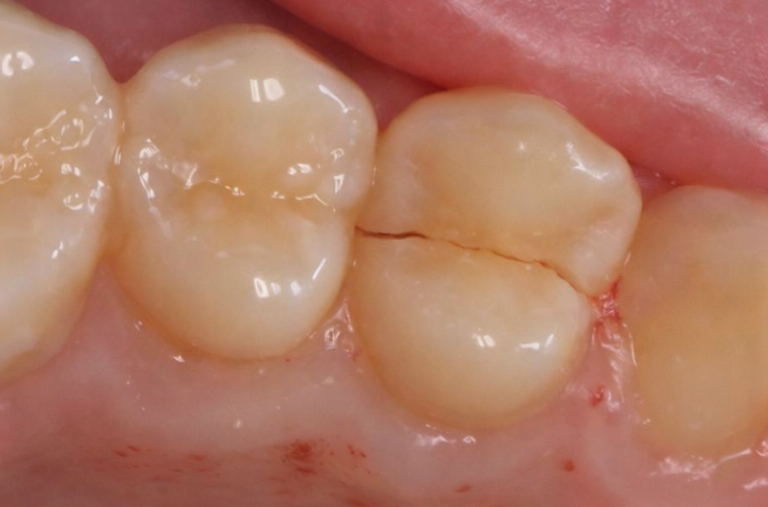

크거나 오래된 충전물이 있는 자연치는

온도 변화에 따라 미세하게 팽창·수축하면서

균열에 더 취약해지기도 합니다.

발산동 치과 구강 정보

CTS가 까다로운 이유는

일반 X-ray로는 균열선이

거의 포착되지 않는다는 점에 있습니다.

이해를 돕기 위한 치아 균열 예시입니다.

균열의 방향이 방사선이

투과하는 방향과 평행할 경우

영상에 나타나지 않기 때문입니다.